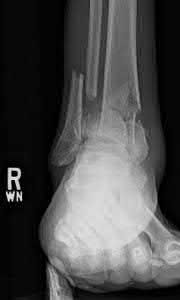

A 25-year-old male sustains an ankle fracture dislocation and undergoes open reduction and internal fixation. He returns to clinic five months following surgery complaining of continued ankle pain and instability with weight bearing. His immediate post-operative AP radiograph is seen in Figure A. Which of the following could have prevented this patient from developing persistent pain?

The patient presents with continued ankle pain and instability following open reduction and internal fixation. The radiograph in figure A demonstrates inadequate restoration of fibular length, likely leading to continued tibiotalar instability.